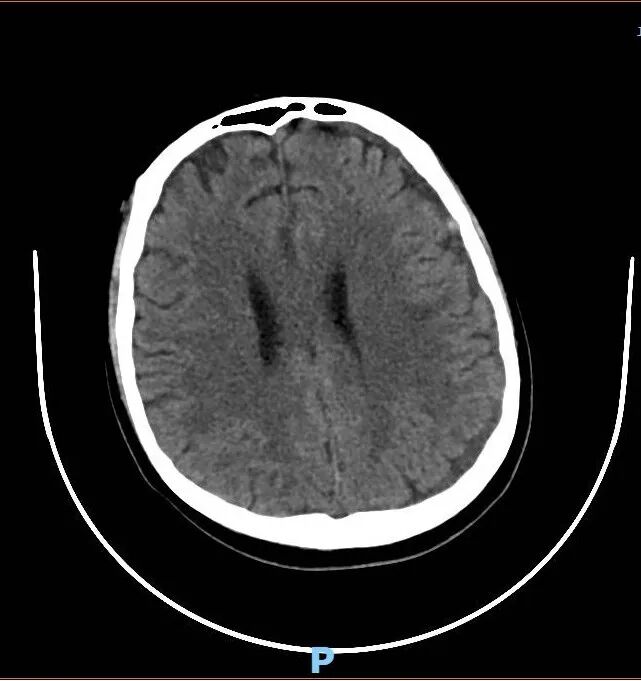

头颅CT显示:颅内大出血,血肿正在压迫大脑中枢。

入院第三天,小程开始出现烦躁、胡言乱语。复查CT显示:血肿扩大,脑组织受压,出现“大脑镰下疝”——这意味着,控制呼吸和心跳的脑干随时可能被压迫,导致呼吸心跳骤停。

半个多月里,医护人员日夜守护,奇迹悄然发生:凝血功能逐步稳定;头颅CT显示:出血停止,血肿开始吸收;意识恢复,生命体征平稳,小程顺利转回普通病房。